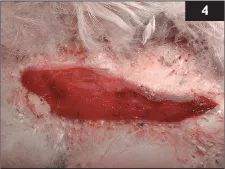

4 You are presented with a young adult mute swan found this morning by the side of a road. The weather is wet and windy. On examination the swan has a slightly wide-based gait, is moderately underweight and has scuffed plantar feet and hocks, a wound on the skin over the keel bone and some bruising to the upper bill. The appearance of the wound, several days after dƩbriding, is shown (4).

i. What are the possible differential diagnoses for this individual?

iii. How would you treat such a wound in this species?

4 i. This has been caused either by a single traumatic event or because of a period of time spent in ventral recumbency on hard surfacing. The history is strongly suggestive of impact trauma (swans may land on wet roads, mistaking them for water) given the typical foot lesions.

ii. Swans suffering from lead poisoning are more likely to fly into power cables and other objects. It would therefore be advisable to screen for lead poisoning by gizzard radiography and blood lead analysis. Survey radiographs, especially of the pelvis, would be advised given the gait abnormality.

iii. The wound appears relatively superficial and to be healing well after dƩbridement. Protective dressings, adherent to the skin or sutured into place, encourage granulation and offer physical protection while helping to keep the wound clean. More chronic or deeper wounds are challenging to treat. They may require repeated dƩbridement, possibly even including bone. Avian skin is thin and inelastic; this area continues to be traumatized by contact with substrate, and the keel bone itself applies further localized pressure to the healing area. Thick bedding, protective dressings, systemic antibiosis and analgesia are all helpful. Swans rarely self-mutilate. The prognosis is guarded.